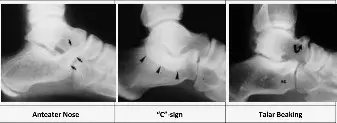

تُعد الأشعة السينية (X-rays) الخطوة الأولى في تقييم آلام الكاحل المشتبه بها، ويمكن أن تكشف عن علامات ائتلاف عظام الرسغ. تُطلب عادةً ثلاث صور: أمامية خلفية، جانبية، ومائلة (Internal Oblique).

- صورة الأشعة المائلة (Internal Oblique View): تُعد الأفضل لتصوير ائتلاف العقب والزورقي.

-

صورة الأشعة الجانبية (Lateral View):

يمكن أن تظهر علامات ثانوية مرتبطة بائتلاف عظام الكاحل والعقب، مثل:

- "أنف آكل النمل" (Anteater Nose Sign): وهو امتداد للناتئ الأمامي لعظم العقب يتجاوز المفصل بين العقب والمكعبي، ويُشاهد في ائتلاف العقب والزورقي.

- علامة "C" (C Sign): وهي استمرارية خلفية بين عظم الكاحل والناتئ السندي لعظم العقب (Sustentaculum Tali)، وتنتج عن ائتلاف في الأوجه الوسطى والخلفية للمفصل تحت الكاحل. ومع ذلك، فإن هذه العلامة ليست محددة دائمًا.

- منقار الكاحل (Talar Beaking): وهو نتوء عظمي يتشكل على الجزء العلوي الأمامي من رأس عظم الكاحل، وينتج عن زيادة الإجهاد في المفصل الكاحلي الزورقي بسبب محدودية حركة المفصل تحت الكاحل.

الشكل 10-54: النتائج الشعاعية الأولية والثانوية لائتلاف عظام الرسغ على الإسقاط الجانبي.

على الرغم من أن الأشعة السينية مفيدة، إلا أنها قد لا تكشف دائمًا عن ائتلاف عظام الكاحل والعقب بشكل كامل، خاصة إذا كان الائتلاف ليفيًا أو غضروفيًا، أو إذا كان المفصل تحت الكاحل غير مرئي بوضوح.